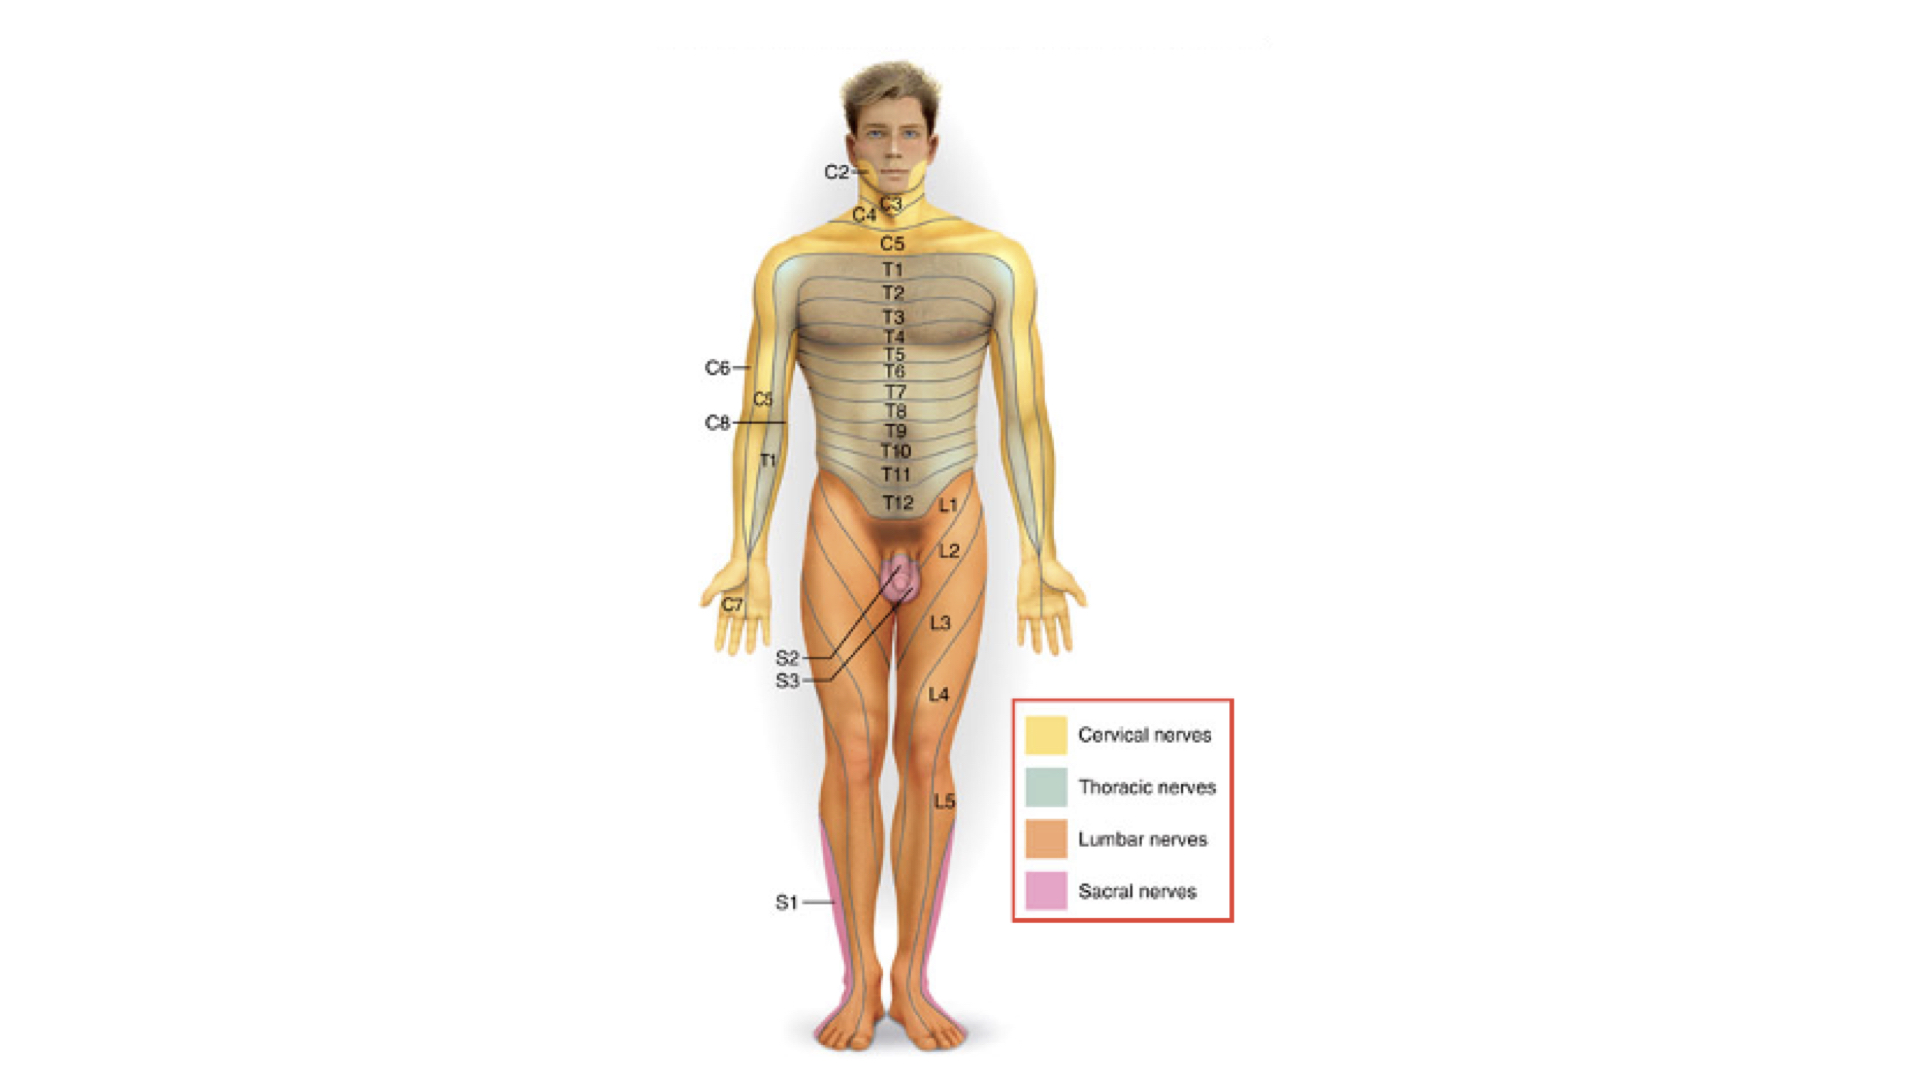

4. As mentioned above, spinal nerves innervate specific areas of the body. These areas are referred to as dermatomes. Below is a mapping of these dermatomes.